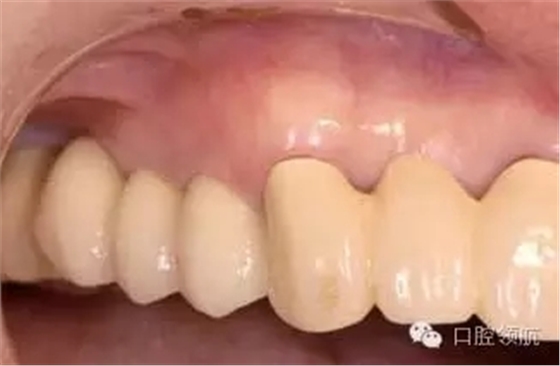

患者因?yàn)椋ㄗ笊系?顆牙) 種植體周?chē)つげ贿m為主訴來(lái)院。(圖1),2年前接受種植治療,每4個(gè)月檢查復(fù)診,但近幾周因身體的不適沒(méi)能堅(jiān)持做好清潔,臨床探診有出血,X線檢查后,沒(méi)有發(fā)現(xiàn)骨吸收現(xiàn)象(圖2)。

圖1 (左上第4顆牙) 種植體周?chē)つび胁贿m感,來(lái)院就診。

圖5 2周后的口內(nèi)情況,周?chē)例l出血消失,狀態(tài)穩(wěn)定。